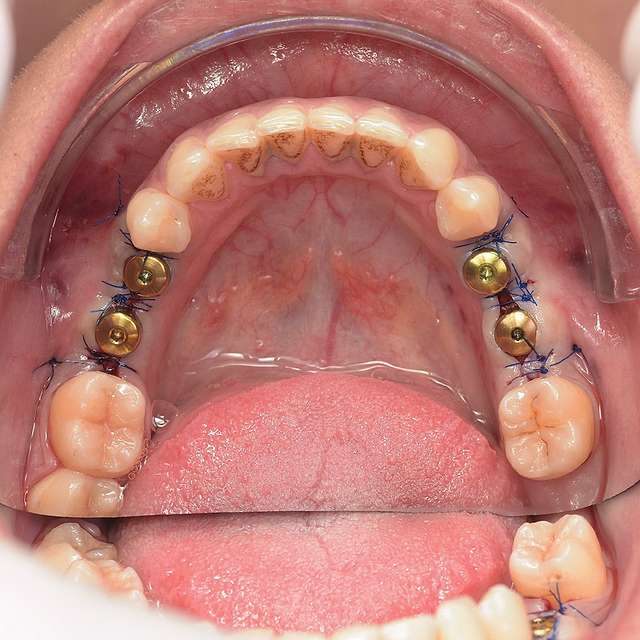

Surgical guides are used for more safety and precision in complex cases that require dental implant therapy. Guides are 3D printed based on the digital planning of the surgery, using specialised software and the CBCT of the patient.

Guided surgery is safe and precise. A surgical guide is recommended in difficult or complex cases, to minimise risks and complications.

When implant therapy is performed with guided surgery, the surgery itself is simpler, and trauma is reduced especially for the soft-tissues. Overall we can achieve faster healing and better post-op comfort.